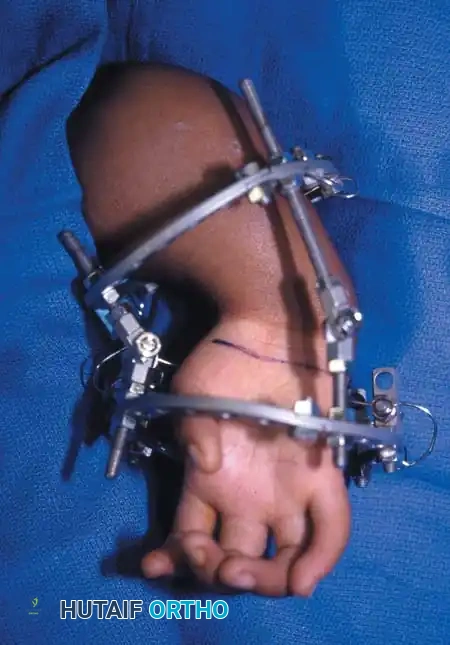

Surgical Interventions in Transverse Deficiencies

Surgical indications for transverse deficiencies are exceedingly rare. Epps, Burkhalter, and McCollough reported that out of 1,077 children